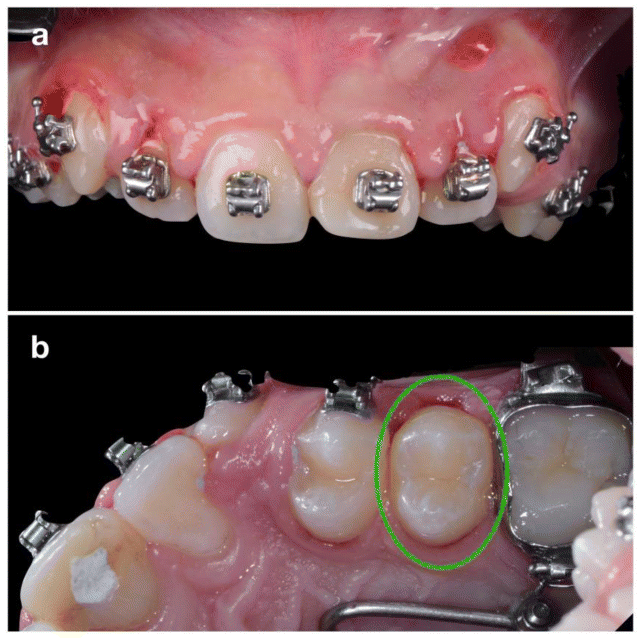

The donor tooth chosen was the maxillary left second premolar (2.5), which presented incomplete root development (Figure 3b). Following six weeks of orthodontic pre-treatment to mobilize and stimulate periodontal tissues (Figure 3), surgical extraction of 2.1 was performed under local anesthesia (Figure 4).

Postoperative management included systemic antibiotics, analgesics, and chlorhexidine rinses. At 10 days, the gingiva appeared healthy with no periodontal probing. At 4 weeks, composite resin was applied to reshape the transplanted premolar into an incisor morphology (Figure 6a). Orthodontic treatment resumed at 8 weeks. After 12 months, CBCT confirmed complete healing without root resorption or periapical pathology (Figure 7). The radiographic images reveal complete resolution of the initial osteolytic lesion and full regeneration of the alveolar socket surrounding the root of the transplanted tooth. Moreover, the vestibular bone wall has entirely reconstituted, closely following the anatomical contour of the tooth root. The contralateral premolar (1.5) was later extracted as part of the orthodontic plan completed in 10 months. Definitive composite restoration was placed after completion of orthodontic treatment (Figure 6b).